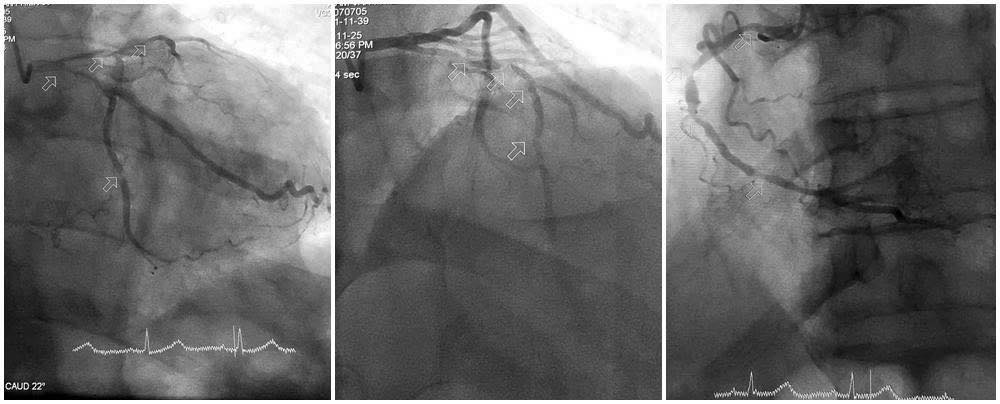

Kết quả chụp mạch vành cho thấy mức độ tổn thương đặc biệt nghiêm trọng: Động mạch liên thất trước hẹp tới 90–99%, gần như tắc hoàn toàn; động mạch mũ và động mạch vành phải hẹp 80–90%; hệ mạch vành vôi hóa nặng, thành mạch cứng, làm tăng nguy cơ biến chứng khi can thiệp.

Ảnh: BVCC

Kíp can thiệp tập trung xử trí tổn thương nặng nhất, luồn dây dẫn qua các đoạn mạch vôi hóa cứng, sử dụng các dụng cụ chuyên dụng để nong bóng từng bước, mở lại lòng mạch bị hẹp nặng.

Việc vượt qua các đoạn mạch vôi hóa là thách thức lớn, song bằng kinh nghiệm, sự kiên trì và phối hợp nhịp nhàng, các bác sĩ đã đặt thành công stent vào động mạch liên thất trước, tái thông dòng máu nuôi tim.